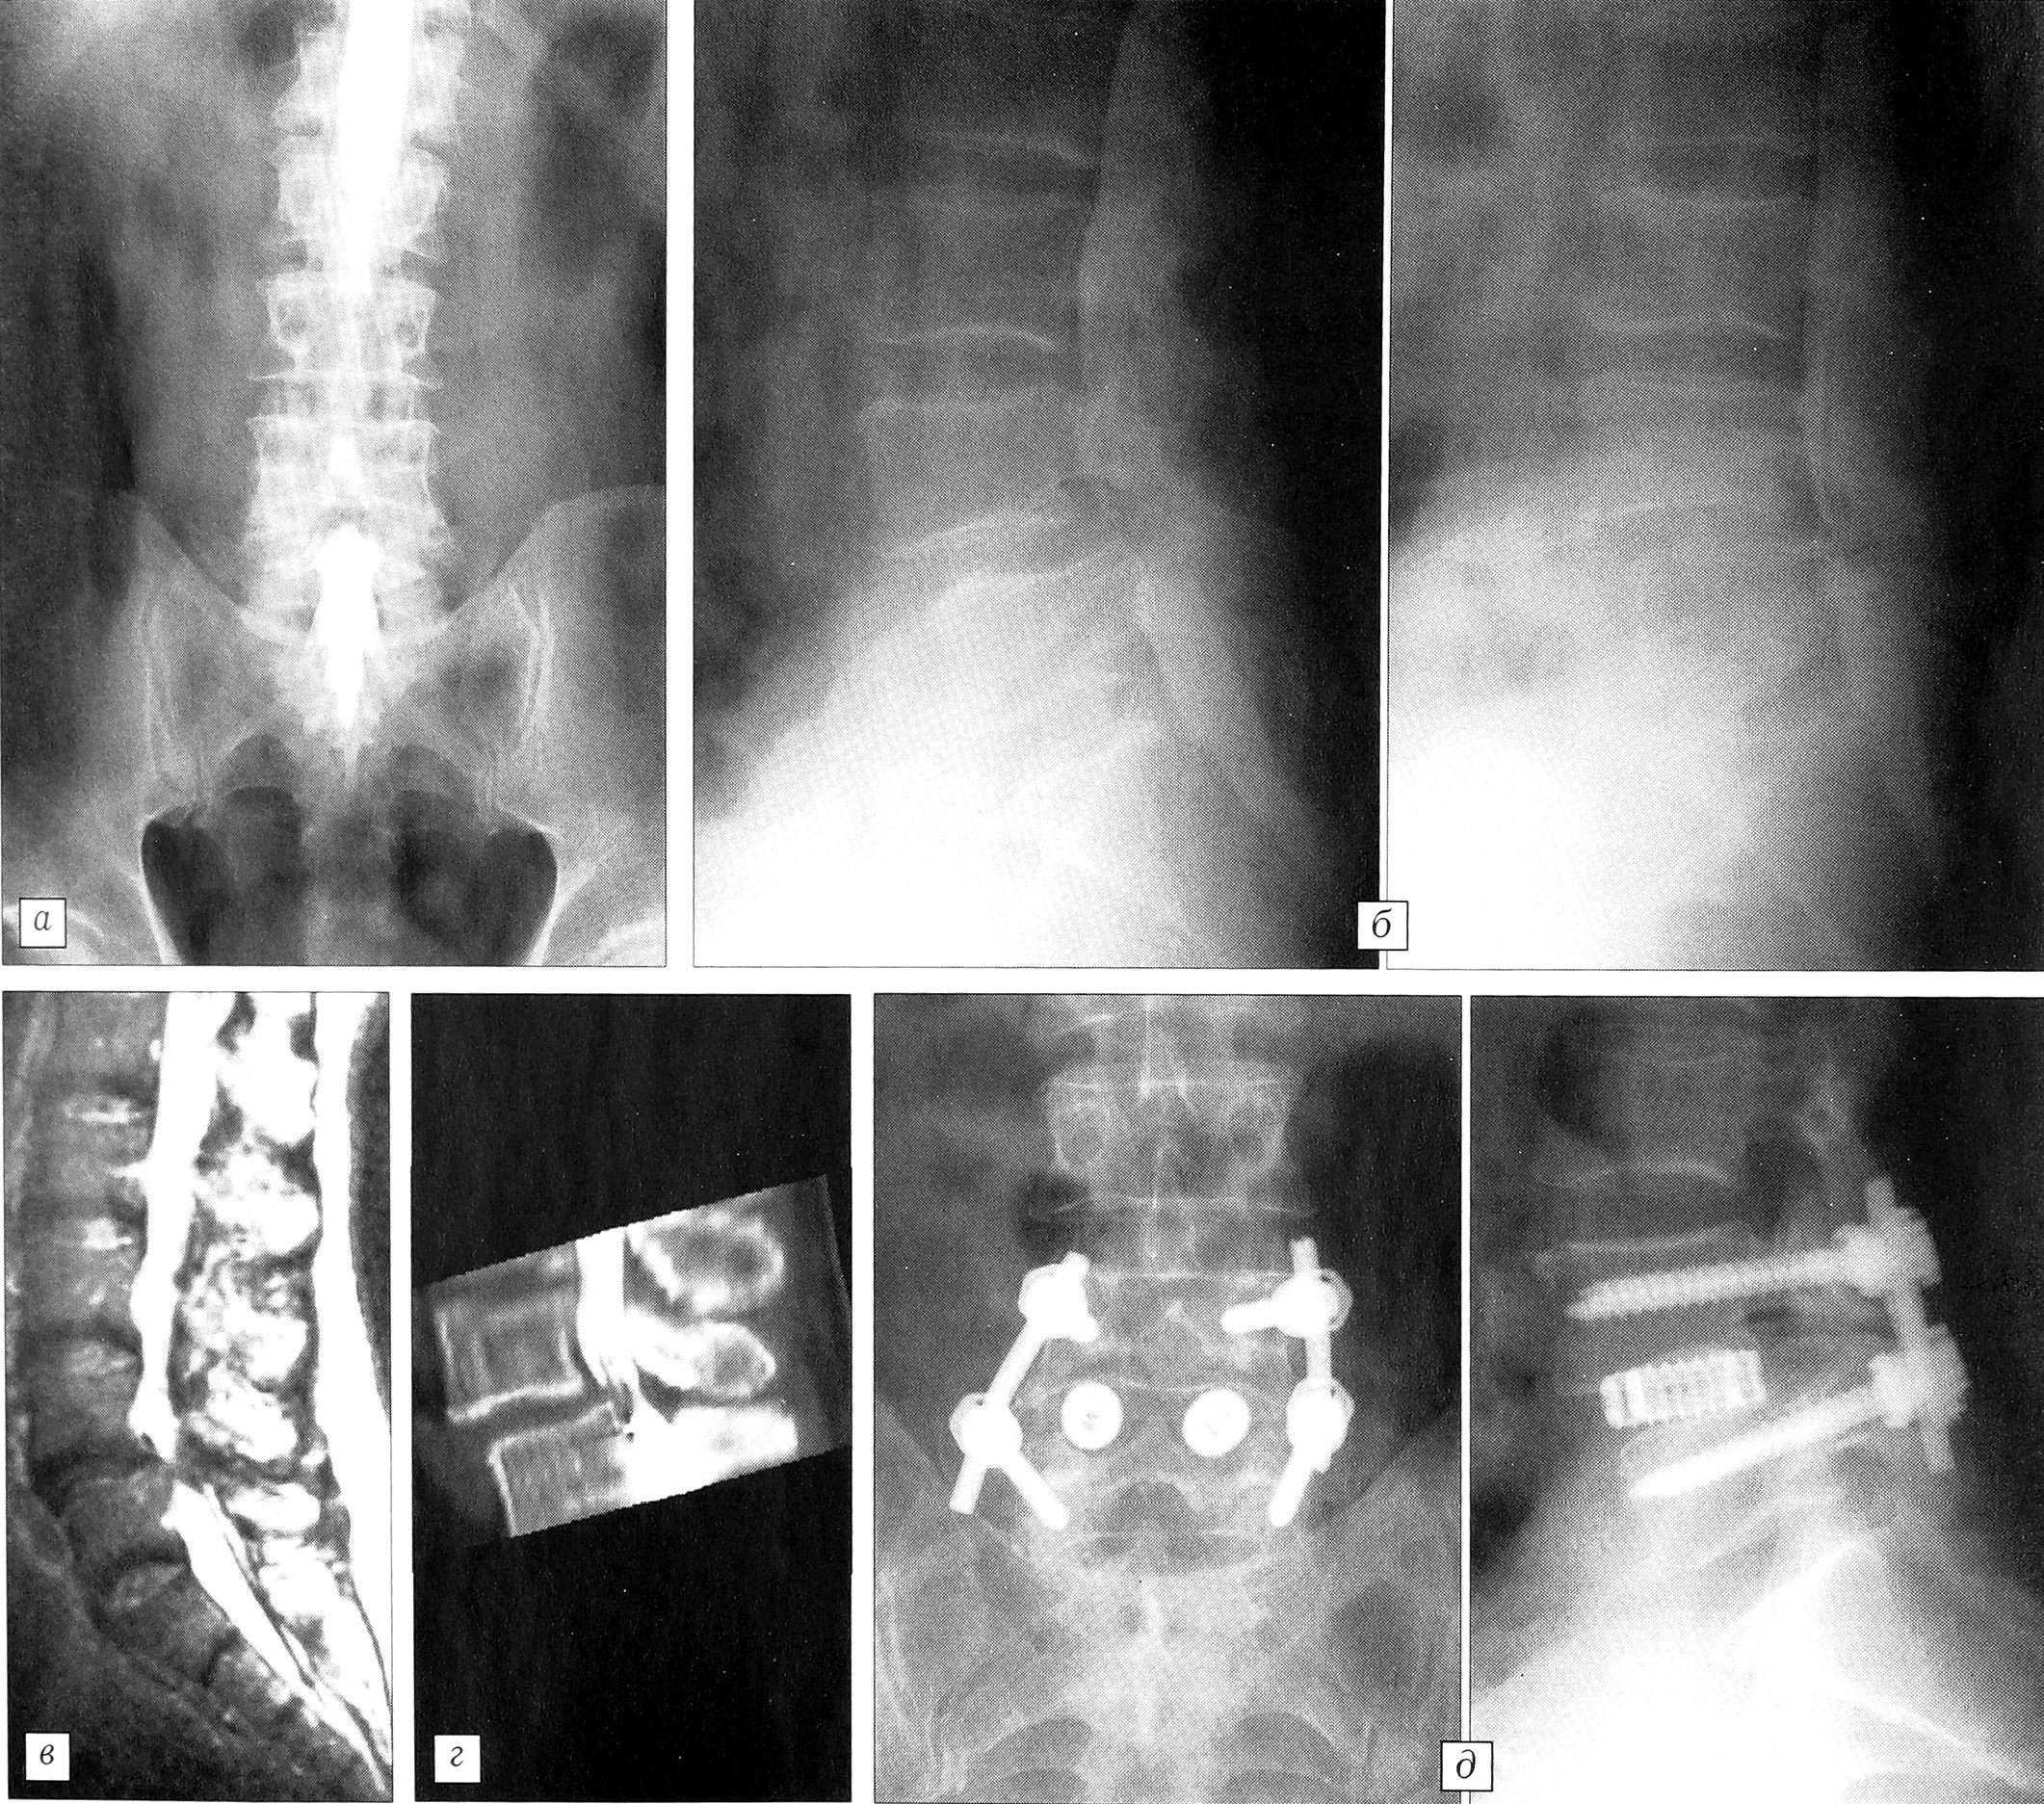

Рис. 4. Больной П. 63 лет. Диагноз: дегенеративный спондилолистез L4 позвонка I степени, вторичный корешковый болевой синдром.

У двух пациентов с дегенеративным спондилолистезом I—II степени и у одного больного, ранее оперированного в другой клинике, у которого сохранялся болевой синдром, а при обследовании был обнаружен перелом транспедикулярных винтов, мы сочетали ТПФ одного сегмента со спондилодезом на 360° из заднего доступа при помощи кейджей (рис. 4). Данная методика позволила провести полноценную ревизию позвоночного канала и стабильную фиксацию с восстановлением высоты межтелового пространства и межпозвонковых отверстий. Клинический и ортопедический результаты во всех трех случаях были хорошими.